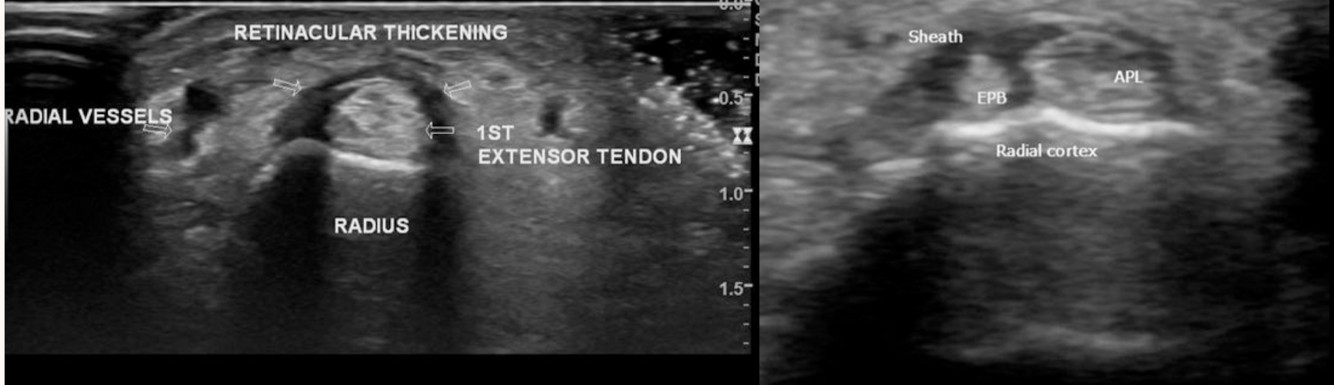

US TSQV

Excelente

engrosamiento e inflamación de los tendones

liquido en su vaina

engrosamiento del retinaculo